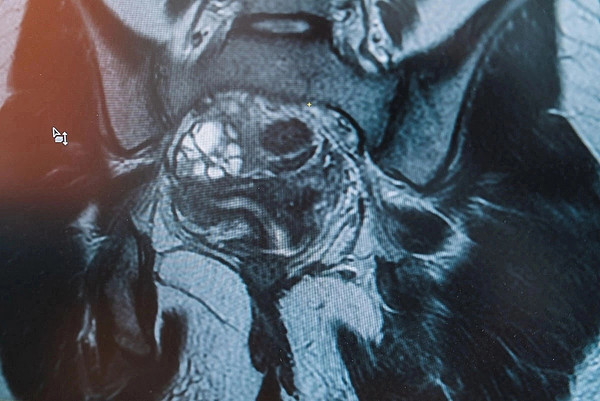

Порядка 8 тысяч исследований провели рентгенологи Кировской детской областной больницы с начала 2023 года